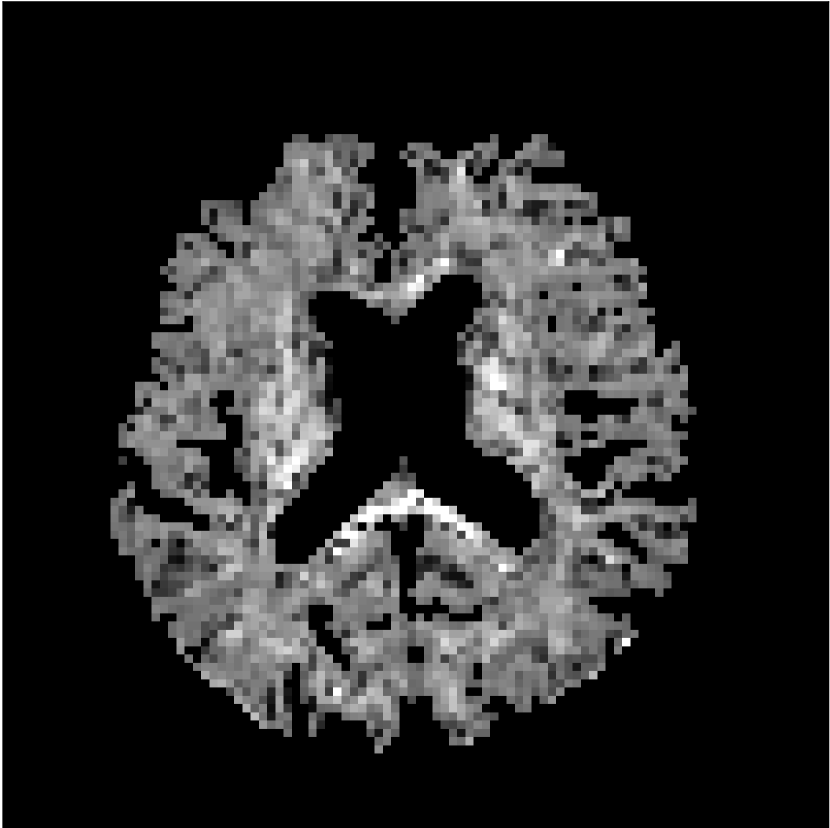

Figure 8 shows examples of non-diffusion-weighted images before and after processing. The raw images (Raw) served as the input for the magnitude deep learning (MCNN) and complex deep learning (CCNN) methods.

Raw

MCNN,

MCNN Resid.,

CCNN,

CCNN Resid.,

No PF

5/8 PF

Both methods remove artifacts, but the MCNN method allows residual rippling artifacts to pass through in the presence of partial Fourier. These rippling artifacts are not present in the CCNN method.